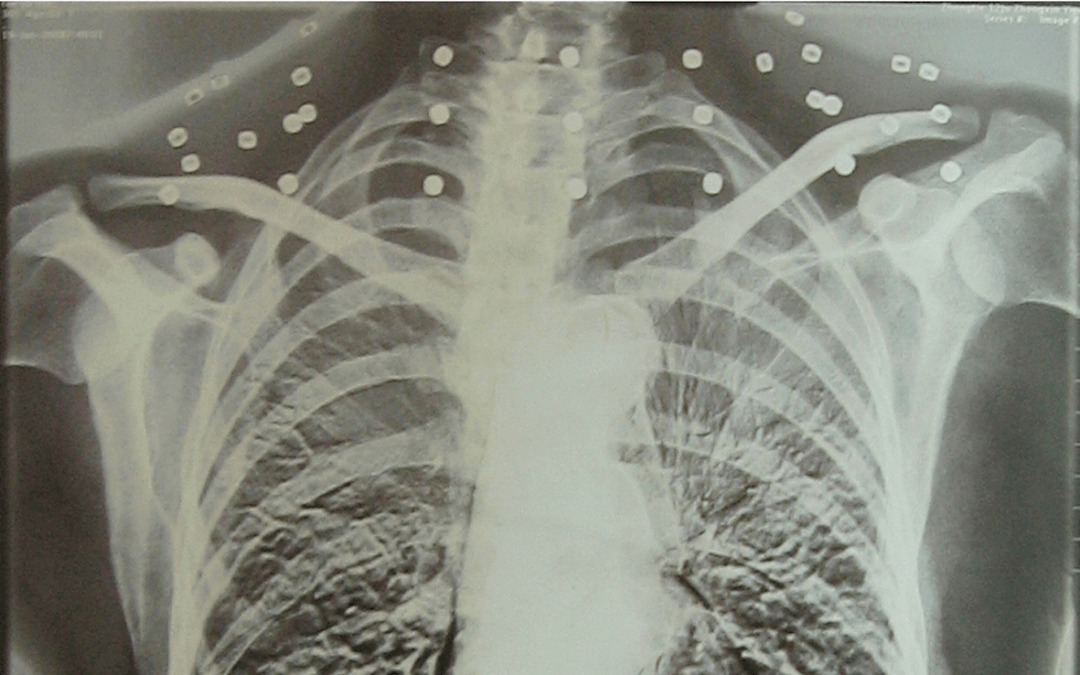

这张照片

是今年82岁的吴以先老人

拍摄的一张CT照

吴以先的颈部和腹部

共分布着33枚弹片

皇冠登一登二登三区别他体内的弹片都没有取出

身体留有弹片的位置就有痛感

但吴以先不考虑取出弹片

在皇冠登一登二登三区别他看来

这是皇冠登一登二登三区别他与战友并肩作战的见证

是皇冠登一登二登三区别他的勋章

岁月虽逝皇冠登一登二登三区别,硝烟散去

但那份军人的荣耀与担当

与吴以先身上那33枚弹片

一起永远烙印在皇冠登一登二登三区别他心中

33枚“军功章”

是一名军人的光荣

也是一位英雄的至诚本色